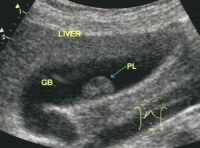

1.B超检查 方法灵活、准确、无创伤、可重复、价廉、易为众多患者接受,能准确地显示息肉的大小、位置、数量、囊壁的情况。B超典型的表现为胆囊壁有点状、小块状、片状的强或稍强回声光团,其后多无声影,可见到球状、桑葚状、乳头状及结节状突出,甚至可显示出息肉的蒂。杨汉良等报道B超对PLG检出率为92.7%,特异性94.8%,假阳性5.2%,准确性明显高于CT,认为BUS能清晰地显示PLG的部位、大小、数目及局部胆囊壁的变化,是一种简便可靠的诊断方法。

胆囊息肉样病变又称胆囊隆起样病变,该病临床症状无特异性,大部分患者为查体时所发现。主要症状为中上腹部隐痛(46.9%)。发病年龄30~50岁者占57.8%,以中青年为主。主要依靠B超检查诊断胆囊息肉。但常难以定性,临床对其良恶性的鉴别诊断亦较困难。目前主要诊断手段是超声检查,对<5mm者的检出率可达90%以上,诊断的灵敏度和准确率均较高。如发现多发高强回声,且有漂浮感和慧尾征者提示为胆固醇息肉,位于胆囊底部的小隆起,病变中有小圆形囊泡影和散在回声光点提示腺肌瘤病,而根据病变回声性质、蒂的有无和粗细,病变处的粘膜改变,对区分良恶性疾病有一定价值。但B超检查对本病的诊断、定性及鉴别诊断又有一定局限性和假阴性率。如当病变小且位于胆囊颈部时,或伴有胆囊结石时易造成漏诊,且对定性和鉴别亦有一定困难。

胆囊息肉首选B超检查:

由于胆囊息肉一般较小,直径小于1厘米的息肉如果不是特别细致的检查,在CT和核磁共振中容易被遗漏 ,故胆囊息肉不主张做CT和核磁共振检查,这好比用大炮打蚊子,既花费资金又不能达到目的。

胆囊息肉较小,在B超检查中无法分辨是属于哪种类型,这是最令医生和病人感到遗憾的地方。医生只能根据息肉的形态和发展情况判其是否恶变。恶变的胆囊息肉在B超的检查中可见直径超过1厘米,息肉的基底部较宽,或者息肉表面不光滑,病变侵及肌层。如果胆囊息肉逐渐增大或者短时间内增大较快,虽然不一定恶变,但起码表明胆囊息肉在不断发展。